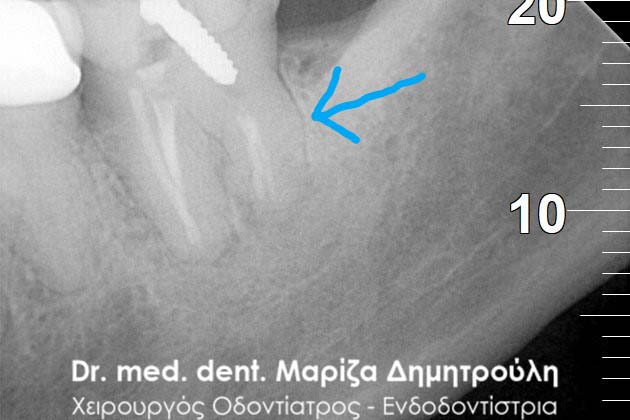

Περιστατικό – Απονεύρωση δοντιού με διάτρηση

Έγινε η κλινική και ακτινογραφικά εξέταση του δοντιού. Στην αρχική ακτινογραφία που πραγματοποιήθηκε πριν τη διάνοιξη του δοντιού παρατηρήθηκε ο έντονος εκτροχισμός του δοντιού ανάμεσα στις ρίζες. Η ακτινογραφική αυτή εικόνα γεννά υποψίες για πιθανή διάτρηση του δοντιού στο συγκεκριμένο σημείο. Διάτρηση ενός δοντιού κατά τη διάρκεια της απονεύρωσης μπορεί να προκληθεί όταν ο οδοντίατρος “ανοίγει” (τροχίζει) το δόντι στην προσπάθεια του να εντοπίσει τις ρίζες του δοντιού (ριζικοί σωλήνες). Είναι δηλαδή πιθανόν το δόντι να τροχιστεί σε άλλο σημείο από αυτό που εντοπίζονται οι ρίζες του δοντιού, με αποτέλεσμα να δημιουργηθεί μία τρύπα στο δόντι. Η τρύπα αυτή ονομάζεται διάτρηση.

Μετά από τη χορήγηση τοπικής αναισθησίας και την τοποθέτηση ελαστικού απομονωτήρα ακολούθησε η διάνοιξη του δοντιού. Αμέσως μετά την αφαίρεση του προσωρινού σφραγίσματος παρατηρήθηκε έντονη και απότομη αιμορραγία του δοντιού, η οποία προερχόταν από ένα συγκεκριμένο σημείο. Η κλινική αυτή εικόνα επιβεβαίωσε τις υποψίες για διάτρηση του δοντιού. Εντοπίστηκε το σημείο της διάτρησης και έγινε έλεγχος με μία ακτινογραφία. Στη συνέχεια πραγματοποιήθηκε η αποκατάσταση της διάτρησης με ειδικό υλικό και εντοπίστηκε ο τρίτος σωλήνας του δοντιού. Η όλη διαδικασία επιβεβαιώθηκε με τη λήψη ακτινογραφίας.

Επιβεβαίωση της διάτρησης